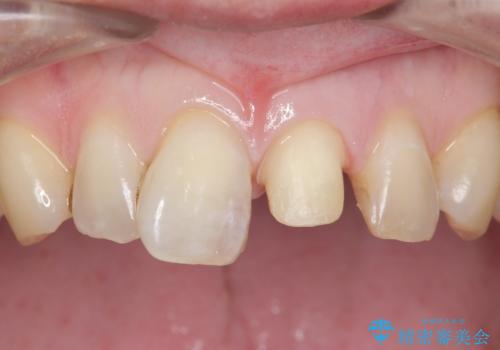

レジンを除去したところ二次う蝕を認めたため、丁寧に虫歯をとりました。

歯の欠損範囲が大きいことから、同様にレジン修復しても欠けやすいためセラミッククラウンによる補綴を行いました。